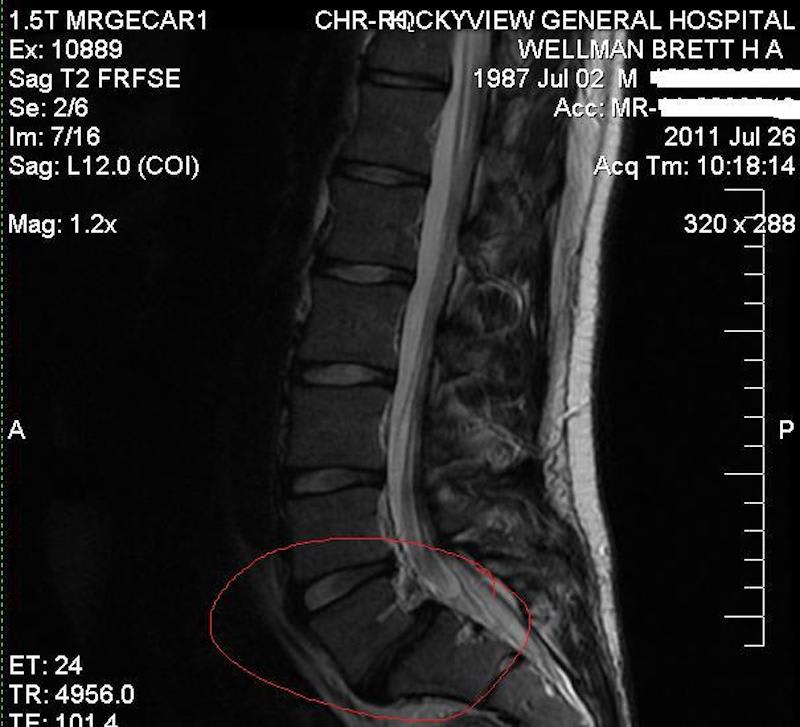

“I was living a life basically for myself,” Brett says, describing his life before 2012. But it was in 2012 that Brett says the Lord “did what it took” to get his attention. “In my case, that was a pretty serious injury to my spine,” he shares.

Medical imaging of Brett’s spinal injury.

“Looking back, I needed something of that magnitude. It got me to really reflect. What is the path of this life I’ve been living? Coming out of surgery, I was way more open to the faith and connecting with people that just really, really cared about each other. I got back into church for the first time in a long time, and then I got baptized and committed my life to Christ. From there, everything began to change.”